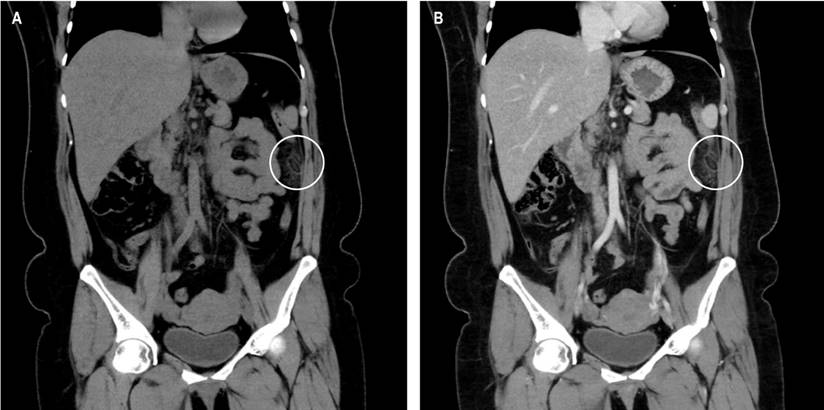

The patient underwent an abdominopelvic computed tomography (CT) with contrast material, which evidenced that the liver, pancreas, spleen, and intestinal loops did not have any significant alteration, the stomach was partially distended with preserved walls and with a hypodense image of the oval fat density of 25 mm x 16 mm that contacts the anterior border of the descending colon, which contains inside a hyperdense image (the sign of the central point) compatible with EA (Figures 1, 2 and 3). She started her medical treatment for pain with diclofenac 75 mg intramuscularly every twelve hours, paracetamol 500 mg orally in only one dose, metronidazole 500 mg orally every eight hours, and simethicone (gaseovet) 15 drops every eight hours. She was indicated to have a soft low-fat diet. The patient was discharged after two days on the following medications: paracetamol 500 mg (10 tablets), tramadol 50 mg (4 tablets), metronidazole 500 mg (9 tablets), and metoclopramide 10 mg (9 tablets).